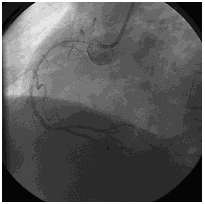

急诊冠脉造影

造影时间:2015年07月19日。

造影前用药:造影前给予替格瑞洛180 mg、肝素3000单位。

造影结果1:右冠近中段原支架未见明显狭窄。

![]()

造影结果2:左主干正常,左前降支近段100%闭塞,回旋支中远段80%~90%狭窄。

造影结论及应对策略:本病例行冠脉造影发现: 右冠近中段原支架未见明显狭窄,左主干正常,左前降支近段100%闭塞,回旋支中远段80%~90%狭窄。立即行前降支PCI术。